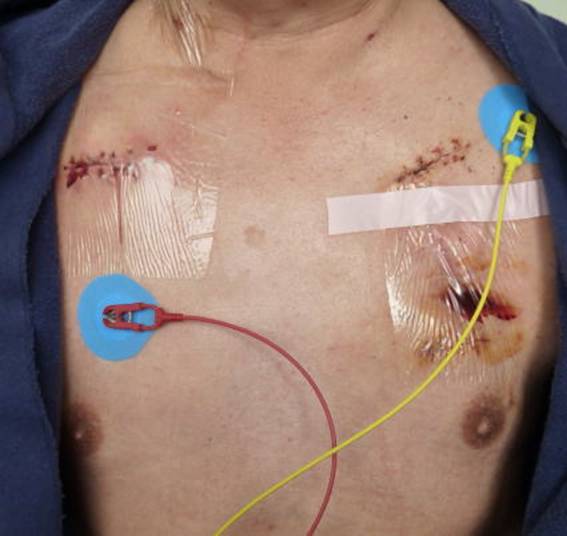

先週(1/23)に続き、第6回目の右胸への新規植え込み術だ。

ペースメーカーは、BIOTRONIK社製、エヴィア(Evia DR-T電池寿命14年)に替わった。ホームモニターリングをし、ドイツにあるセンターへPMのロギングデータを夜中に毎日送る。MRIにも耐えるということだが、日本では承認されていない。

が、先生一言も発せず、恐らく計器を見ているのだろうと、ふと思った。患者は初めての経験を伝えるべくもなく、万事休すかと。脈数からして、5秒から6秒程の出来事か。

心房リードもカウントしながらスクリューイン。結果としては、安心感が一々の手際から伝わる手術だった。

“悔いの無いように”と先生、縫合前に何度か消毒する、と書いている時(11:15)、左胸に冷たく流れる感触。下着が液で染まる。溜まっていた液が透明テープの皺の隙間から洩れたのだ。患部を湿潤に保つのが近頃の医療判断なのだ。漏れた後もたっぷりではないが液が少し残っている。看護師さんに連絡。テープでというから、替わりにガーゼを当ててもらった。テープは気触れる。

201202031121

201202041114

看護師さんが、術後、部屋に戻った時、やり終えたという顔をしている、と評す。が、本心は、新しい悩みに向かって踏み出したとの思いである。ひとつは、左胸の傷、特に穴の開いた箇所が同様のことを繰り返すのか、それは血流の過程で右胸を侵さないのか。次に、右胸、新規のペースメーカー植え込み後の感染の憂慮だ。が、不確かの中、一々を決定しながら生きる道程と、割り切って考えてもいた。

両方の手術箇所が夫々の痛みを発する。先ず左は穴の辺りがチクチクと。右胸は擦れるようなちょっと重い痛み。看護師さんが言うには。ポケットを創り、ペースメーカーを入れるため抉った時の傷が痛むのではと。妙に納得。0から5の段階に分けての顔表示で、痛みを示す。どれ位かと、1の段階の顔表示を選ぶ。

20:25 S先生。傷口を診る。PMチェックの件を告げる。H先生から聞きましたと。今のところ液が出ていない。左は先生の中縫いが効きましたかね、と。

201202091405 (画面左側 テープ気触れ)

201202092101.JPG(半抜糸の状態)

201202092110 以上三点自分で撮影。

20120210114501

20120210114502

20120210114601

20120210114602

201202132330(右胸PM植込み後)

201202132331 (左胸PM抜去後)